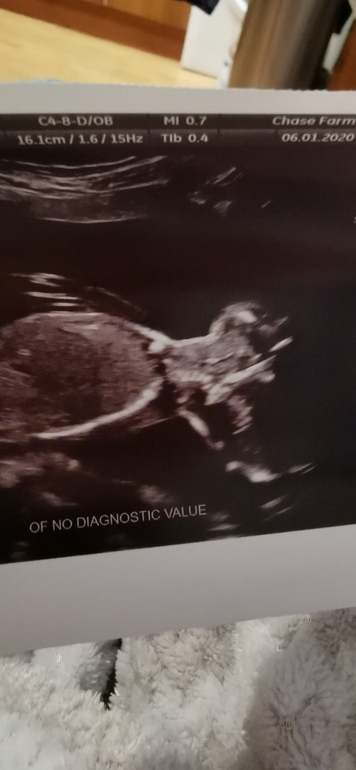

Эмоции, странности, тревогиДевочки сходила на 2 скрининг. Ребенок соответствует сроку развивается хорошо. Но у меня короткая шейка матки 22мм пока наблюдаем каждые 2 недели. Но мне не понравилось фото которое мне дали со скрининга. Почему малыш так голову назад запрокинул. Меня это беспокоит. У врача сразу не спросила теперь переживаю. И сегодня малыш часто очень пинался, я даже устала от этих пинков. Как будто его чтото беспокоило.

Вас наверное поймали, когда малыш выгибался, моя так на мониторе делала, все хорошо💐

Просто фото сделали в момент, когда он голову запрокинул.